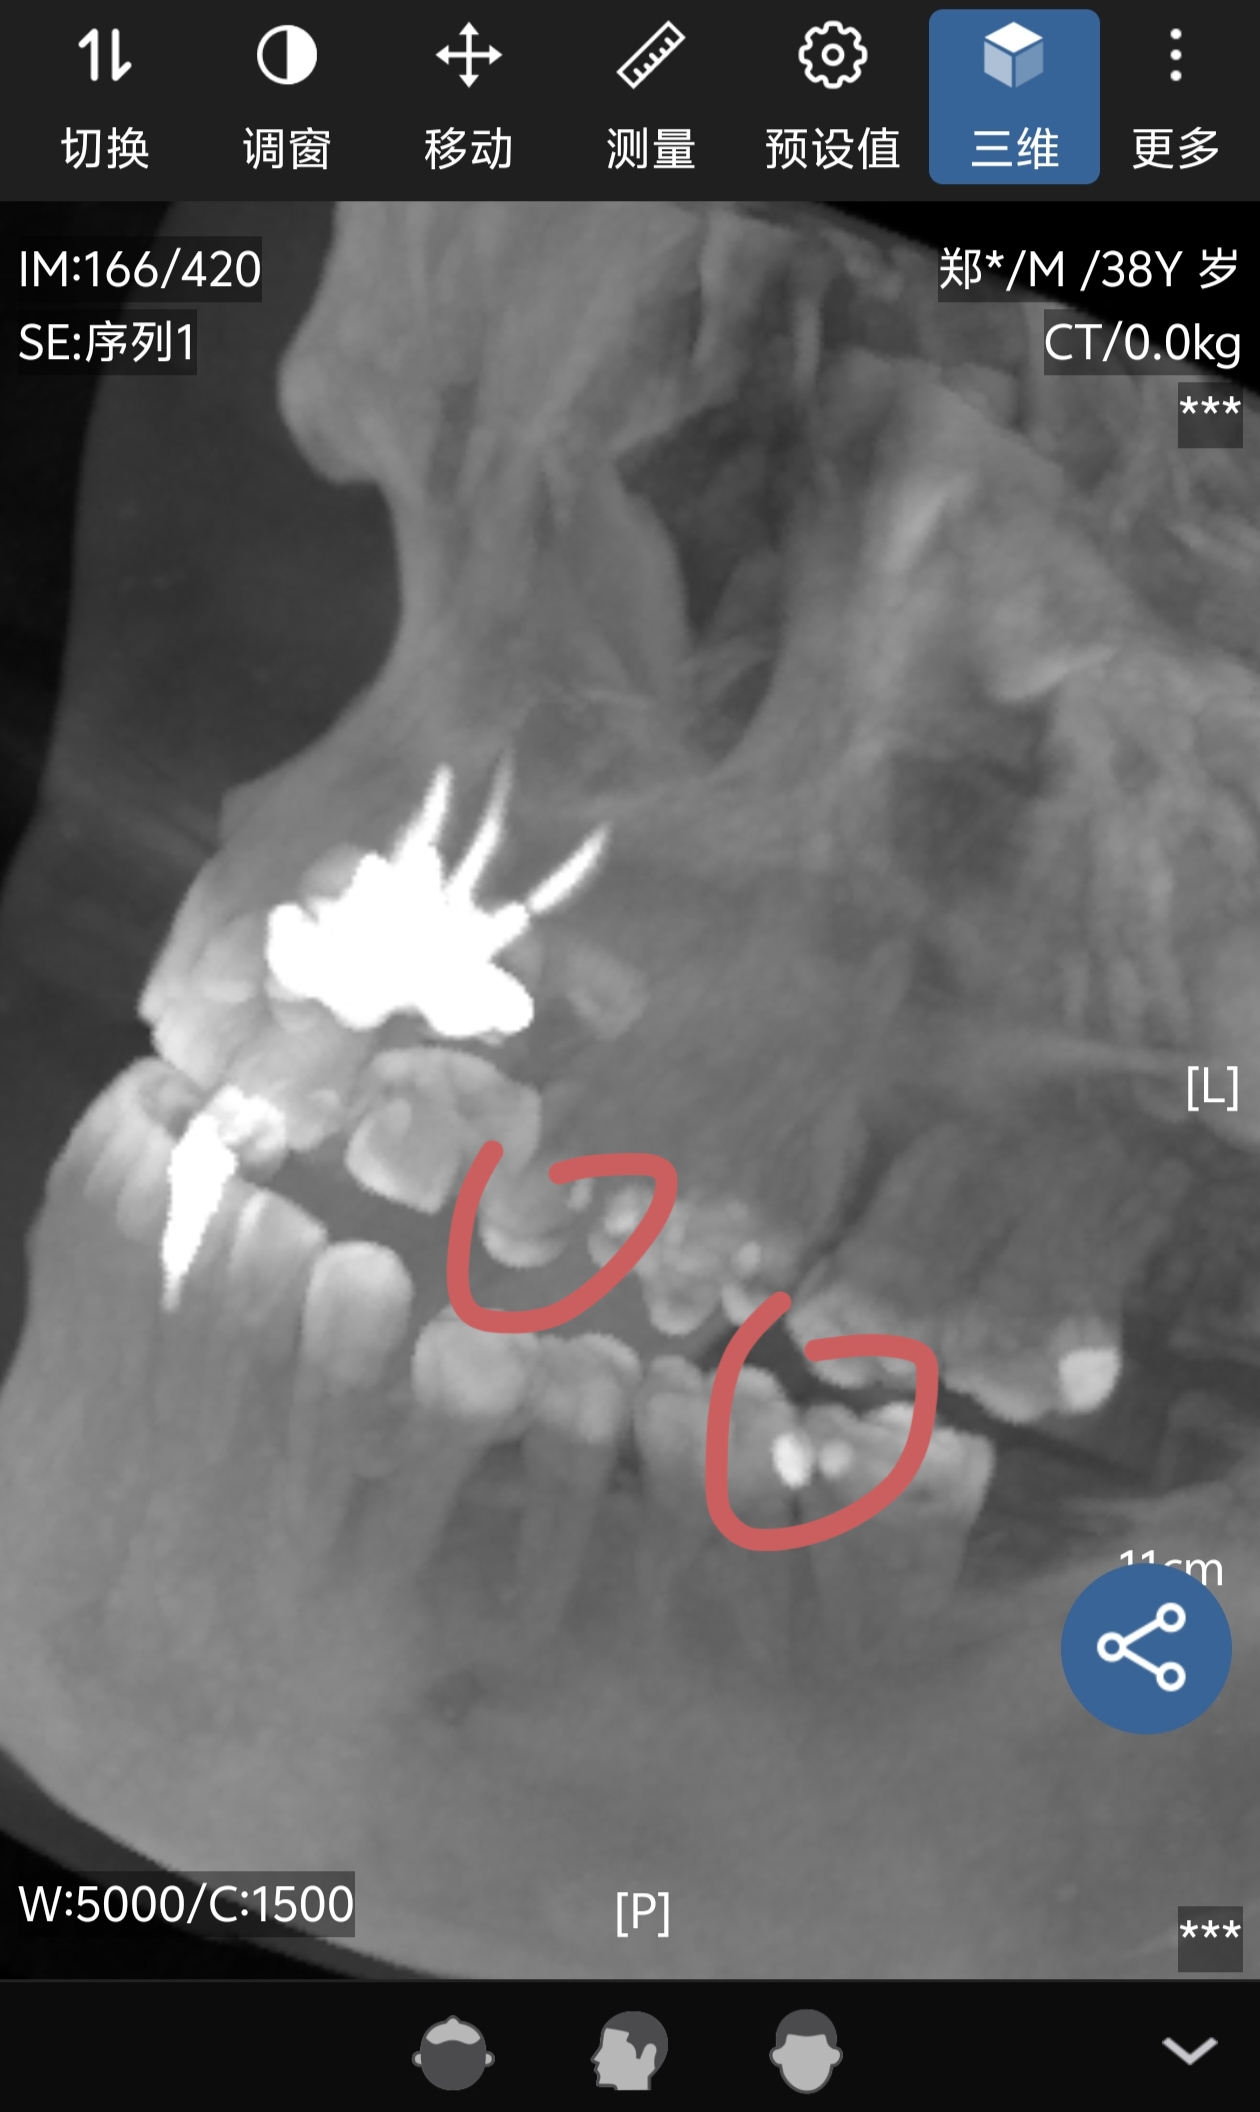

这次特地选择去三甲医院看牙,听说现在国内看牙价格都降了很多,但去三甲是为了不被坑,因为这两颗牙都不知道是不是龋到牙髓了,拍片之后,医生告诉我,这两颗牙都和接近牙髓了,补牙的方案不可行,那就是根管治疗~~~

哎哟我去,又保不住了~~然后看了看旁边最后那可大牙,说可能也有蛀牙,后面又说,如果当初补牙的给里面放药,药也可能被识别为蛀牙的阴影,所以...还不确定,还有这样的啊~~

是这样的,左上边双尖牙三甲医院拍片后,又给她看了一下牙,说我上边这个颗牙估计是龋了,说龋了挺深,如果做根管和牙套可能时间来不及,可以看出他们无所谓态度,最好少一个患者对他们上班拿钱来说都是少一份折腾,虽然其实是一样的,但是他们也不装了,一天少折腾就是赚。

后来我拿到外面医生看,他稍微敲了一下我的牙,问我疼么,直接判断神经已经死一半了,我说不疼,但是之前三甲医生的判断是你这牙还没龋到牙髓所以不疼,好吧,里面医生得花1个月多时间才能完成整套,外面医生好像3个星期可能就解决了。